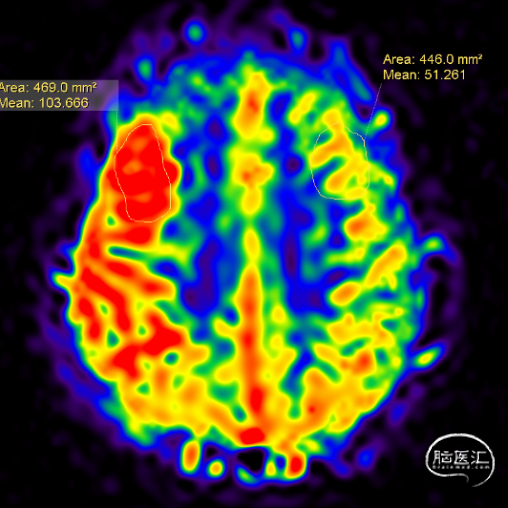

颅脑灌注成像提示高灌。